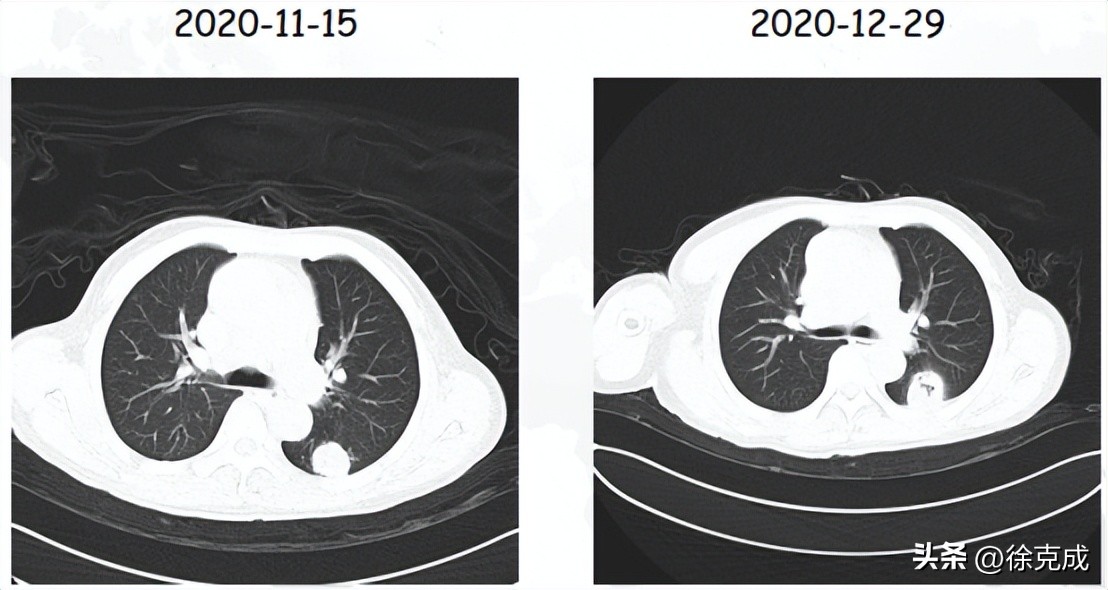

一位来自辽宁的肺腺癌患者,入院时出现呼吸困难,血氧饱和度下降至90%以下;CT检查发现右肺的80%均被炎症占据。无法行相应的抗肿瘤治疗,后吸入氢氧混合气(3L/min),让他病情出现“拐点”,患者呼吸困难缓解。后联合口服靶向药治疗至今。如今,患者正常生活与工作,肺部的病变已得到很好的控制。